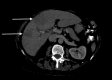

Pylephlebitis is a rare condition with a high mortality risk if not recognized and treated early. The most common symptoms include fever and abdominal pain, with the majority of cases manifesting with a polymicrobial bacteremia. We report an elderly woman with pylephlebitis presenting with fever, abdominal pain, diarrhea, and vomiting, likely secondary to a polypectomy 6 weeks prior. Abdominal CT revealed portal vein thrombus and blood cultures grew Streptococcus milleri and Haemophilus parainfluenza type V. Pylephlebitis should be considered when symptoms and signs of infection develop following endoscopic procedures, particularly in patients with an underlying hypercoaguable disease.